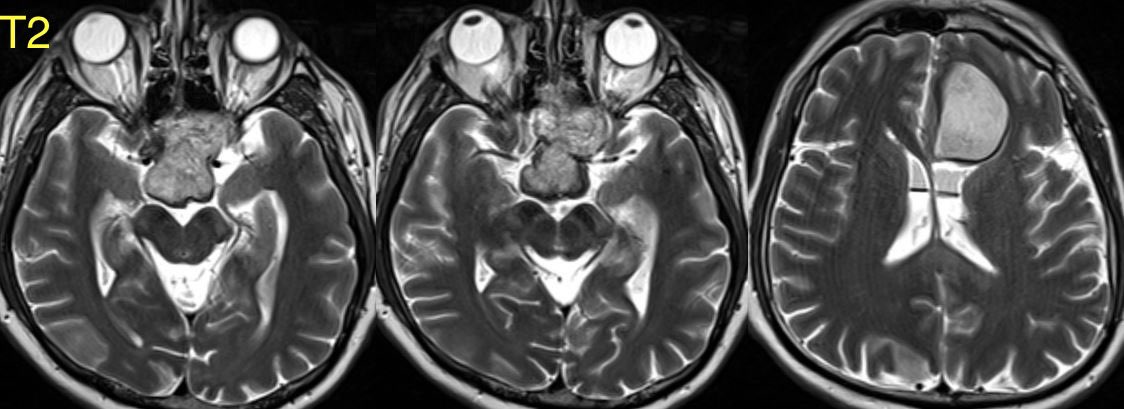

What is the most likely diagnosis in this 30 y/o patient with history of seizures presenting with severe headache?